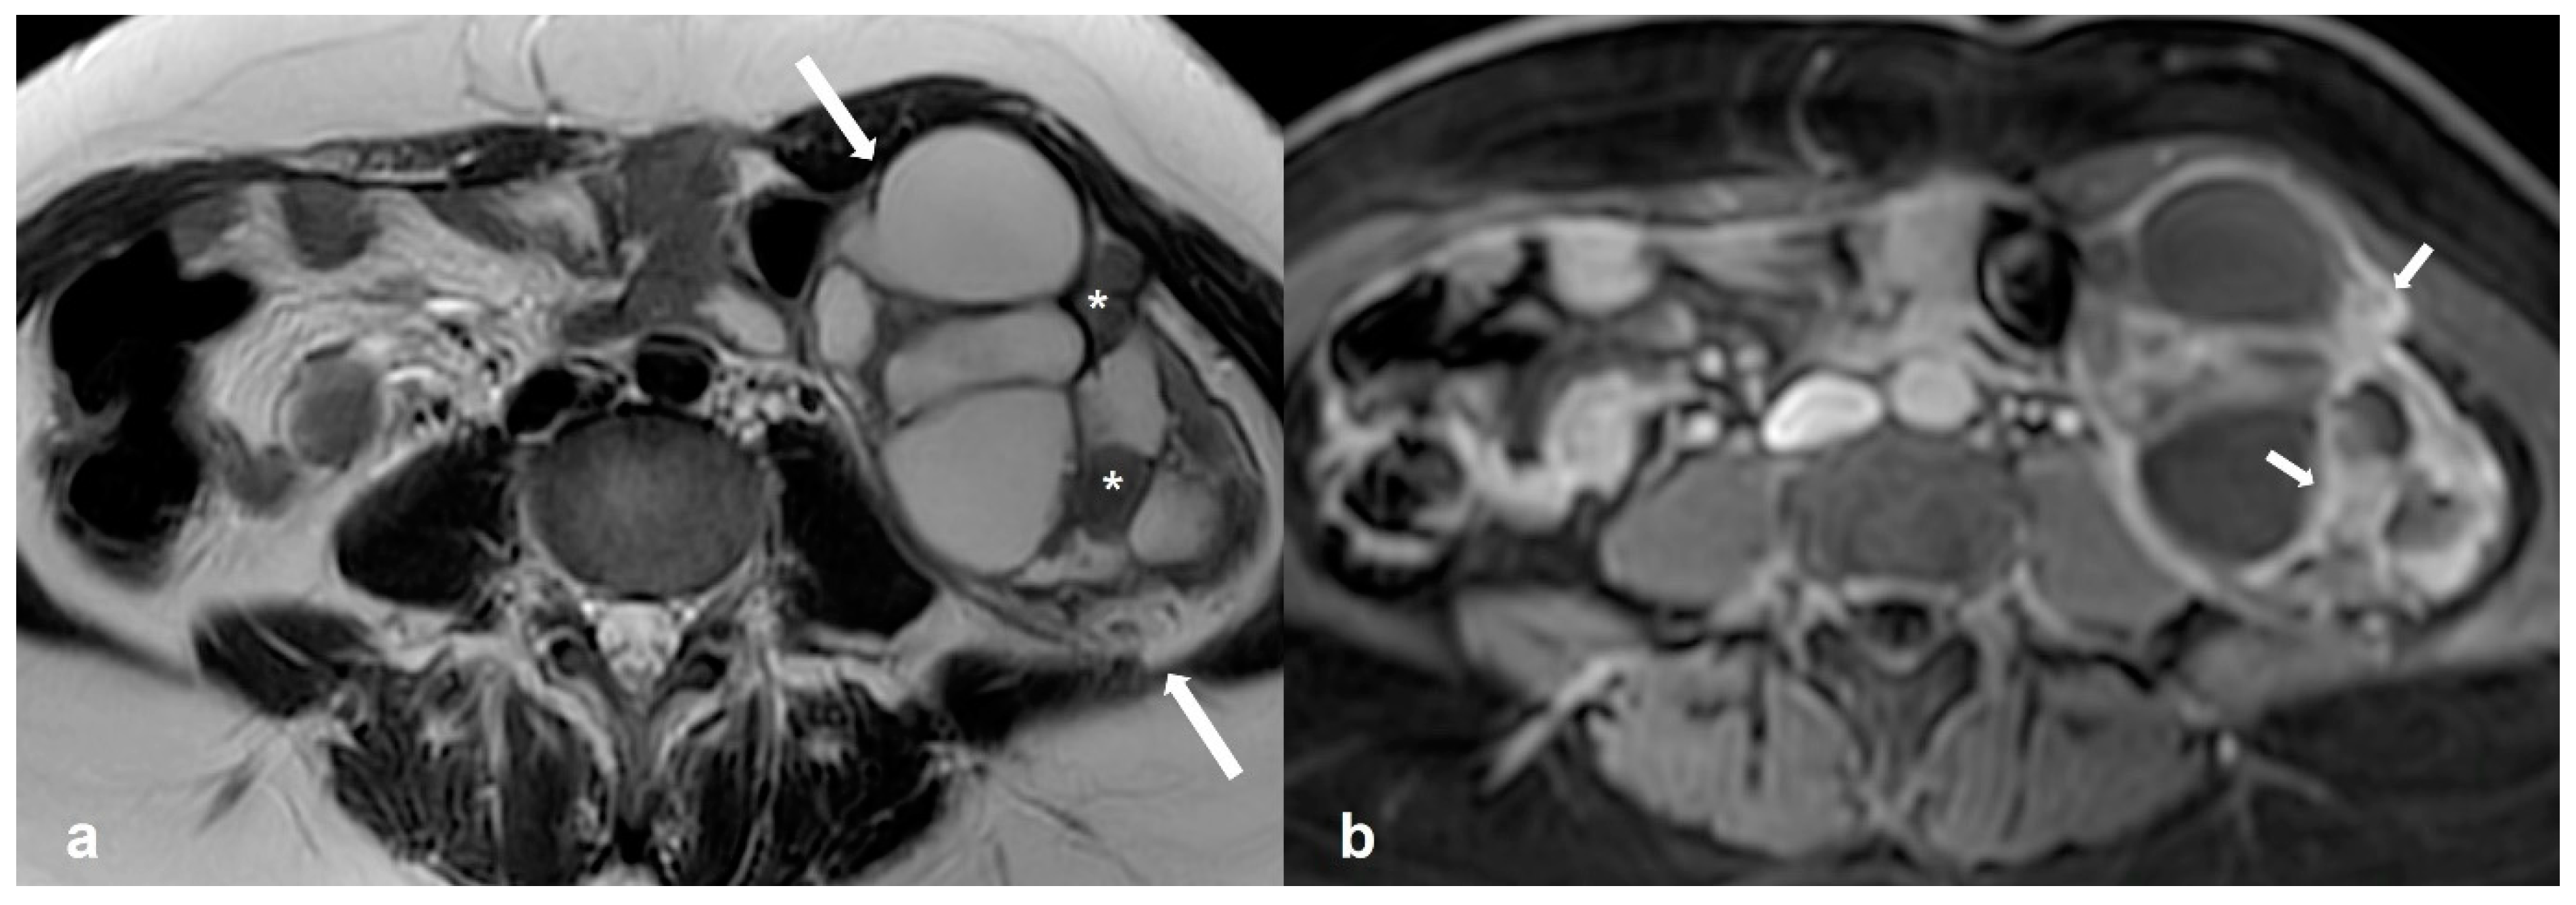

2.2.1. Cystadenofibroma

2.2.2. Fibrothecoma

2.2.3. Pelvic Inflammatory Disease—Tubo-Ovarian Abscess (TOA)